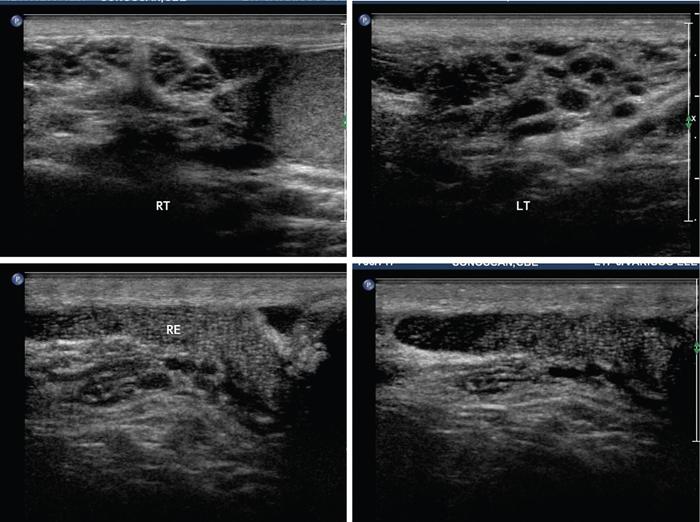

Bobji Kettay The epididymis is positioned in the posterolateral aspect of testis and subdivided into three parts namely, the head, body and tail. Collection and temporary storage of sperms till maturation are its functions. The tail of epididymis continues as the vas deference (Fig. 11.9.1). The epididymis is ideally imaged with USG using a high frequency (7.5 to 10 MHz), linear array, near focused transducer and is best viewed in the longitudinal plane. Its echogenicity is similar to that of testis but echotexture is coarser than testes (Fig. 11.9.2). MRI is a complimentary modality. Epididymis appears slightly heterogeneous and is isointense to testicular parenchyma on T1WI. On T2WI, it shows slightly reduced intensity than testis. Retrograde (ascending) bacterial infection from lower urinary tract is the commonest cause for epididymitis. In sexually active men, <35 years of age, Neisseria gonorrhoea and Chlamydia trachomatis are the causative agents. Escherichia coli is the cause in children and >35 years old. Tail of epididymis is first to get affected because of the ascending nature of the infection. So thorough evaluation of the tail during USG is essential to diagnose the early stage of the disease. Body and head are subsequently involved and the infection can also spread to the testis. Noninfective acute epididymitis is called as chemical epididymitis. This occurs when sterile urine is extravasated into epididymis due to increased intraabdominal pressure during acts like straining. Chemical epididymitis spares the head and affects only the tail of epididymis. Patients present with scrotal swelling, pain, pyuria and fever.